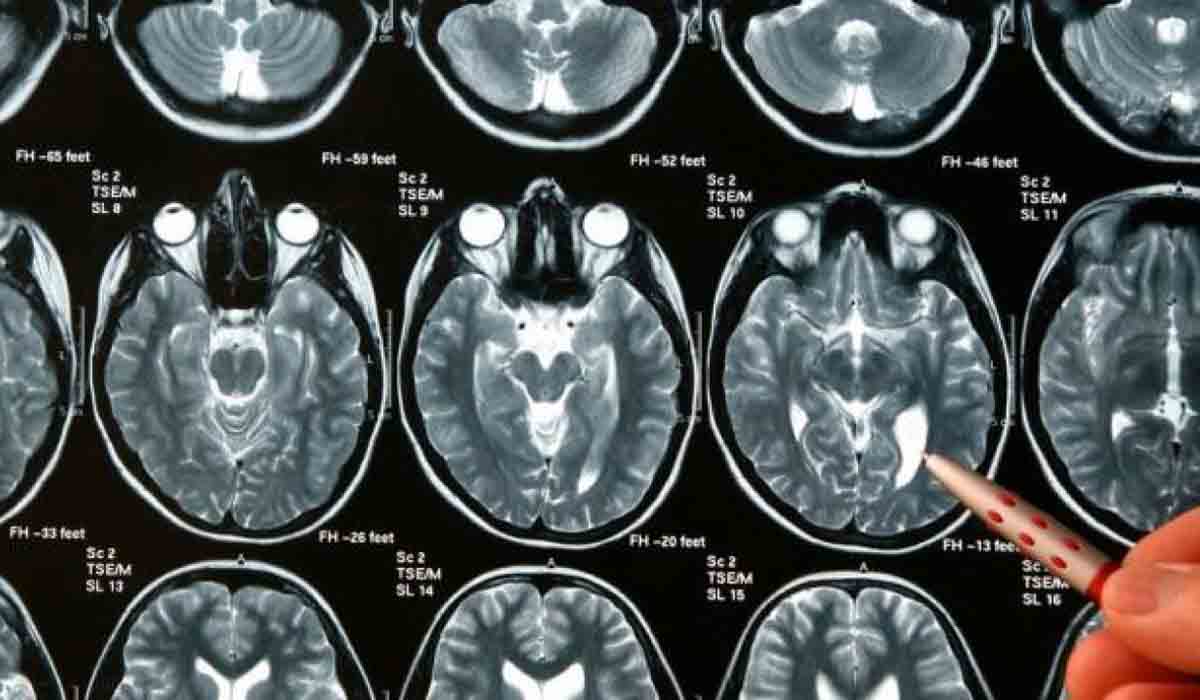

Aunque el meningioma suele ser benigno, la aparición de tumores en el cerebro puede provocar problemas derivados de la presión que ejercen sobre ese órgano. Según el estudio, el riesgo de desarrollar esta enfermedad fue más alto en mujeres mayores de 31 años, así como en aquellas que habían consumido esas hormonas por más de cuatro años.